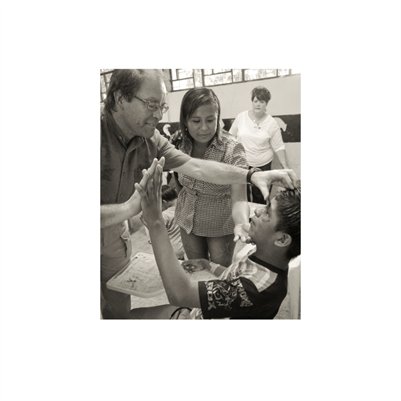

Darkness into the Light. In 2012, The Amazon Project gave eye care to nearly 6000 patients within a 200 kilometer radius of their base in Leticia, Colombia.